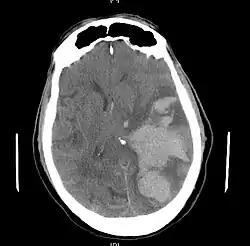

Treatment involves removal of the etiologic mass and decompressive craniectomy. Brain herniation can cause severe disability or death. In fact, when herniation is visible on a CT scan, the prognosis for a meaningful recovery of neurological function is poor.[2] The patient may become paralyzed on the same side as the lesion causing the pressure, or damage to parts of the brain caused by herniation may cause paralysis on the side opposite the lesion.[11] Damage to the midbrain, which contains the reticular activating network which regulates consciousness, will result in coma.[11] Damage to the cardio-respiratory centers in the medulla oblongata will cause respiratory arrest and (secondarily) cardiac arrest.[11] Investigation is underway regarding the use of neuroprotective agents during the prolonged post-traumatic period of brain hypersensitivity associated with the syndrome.[17]